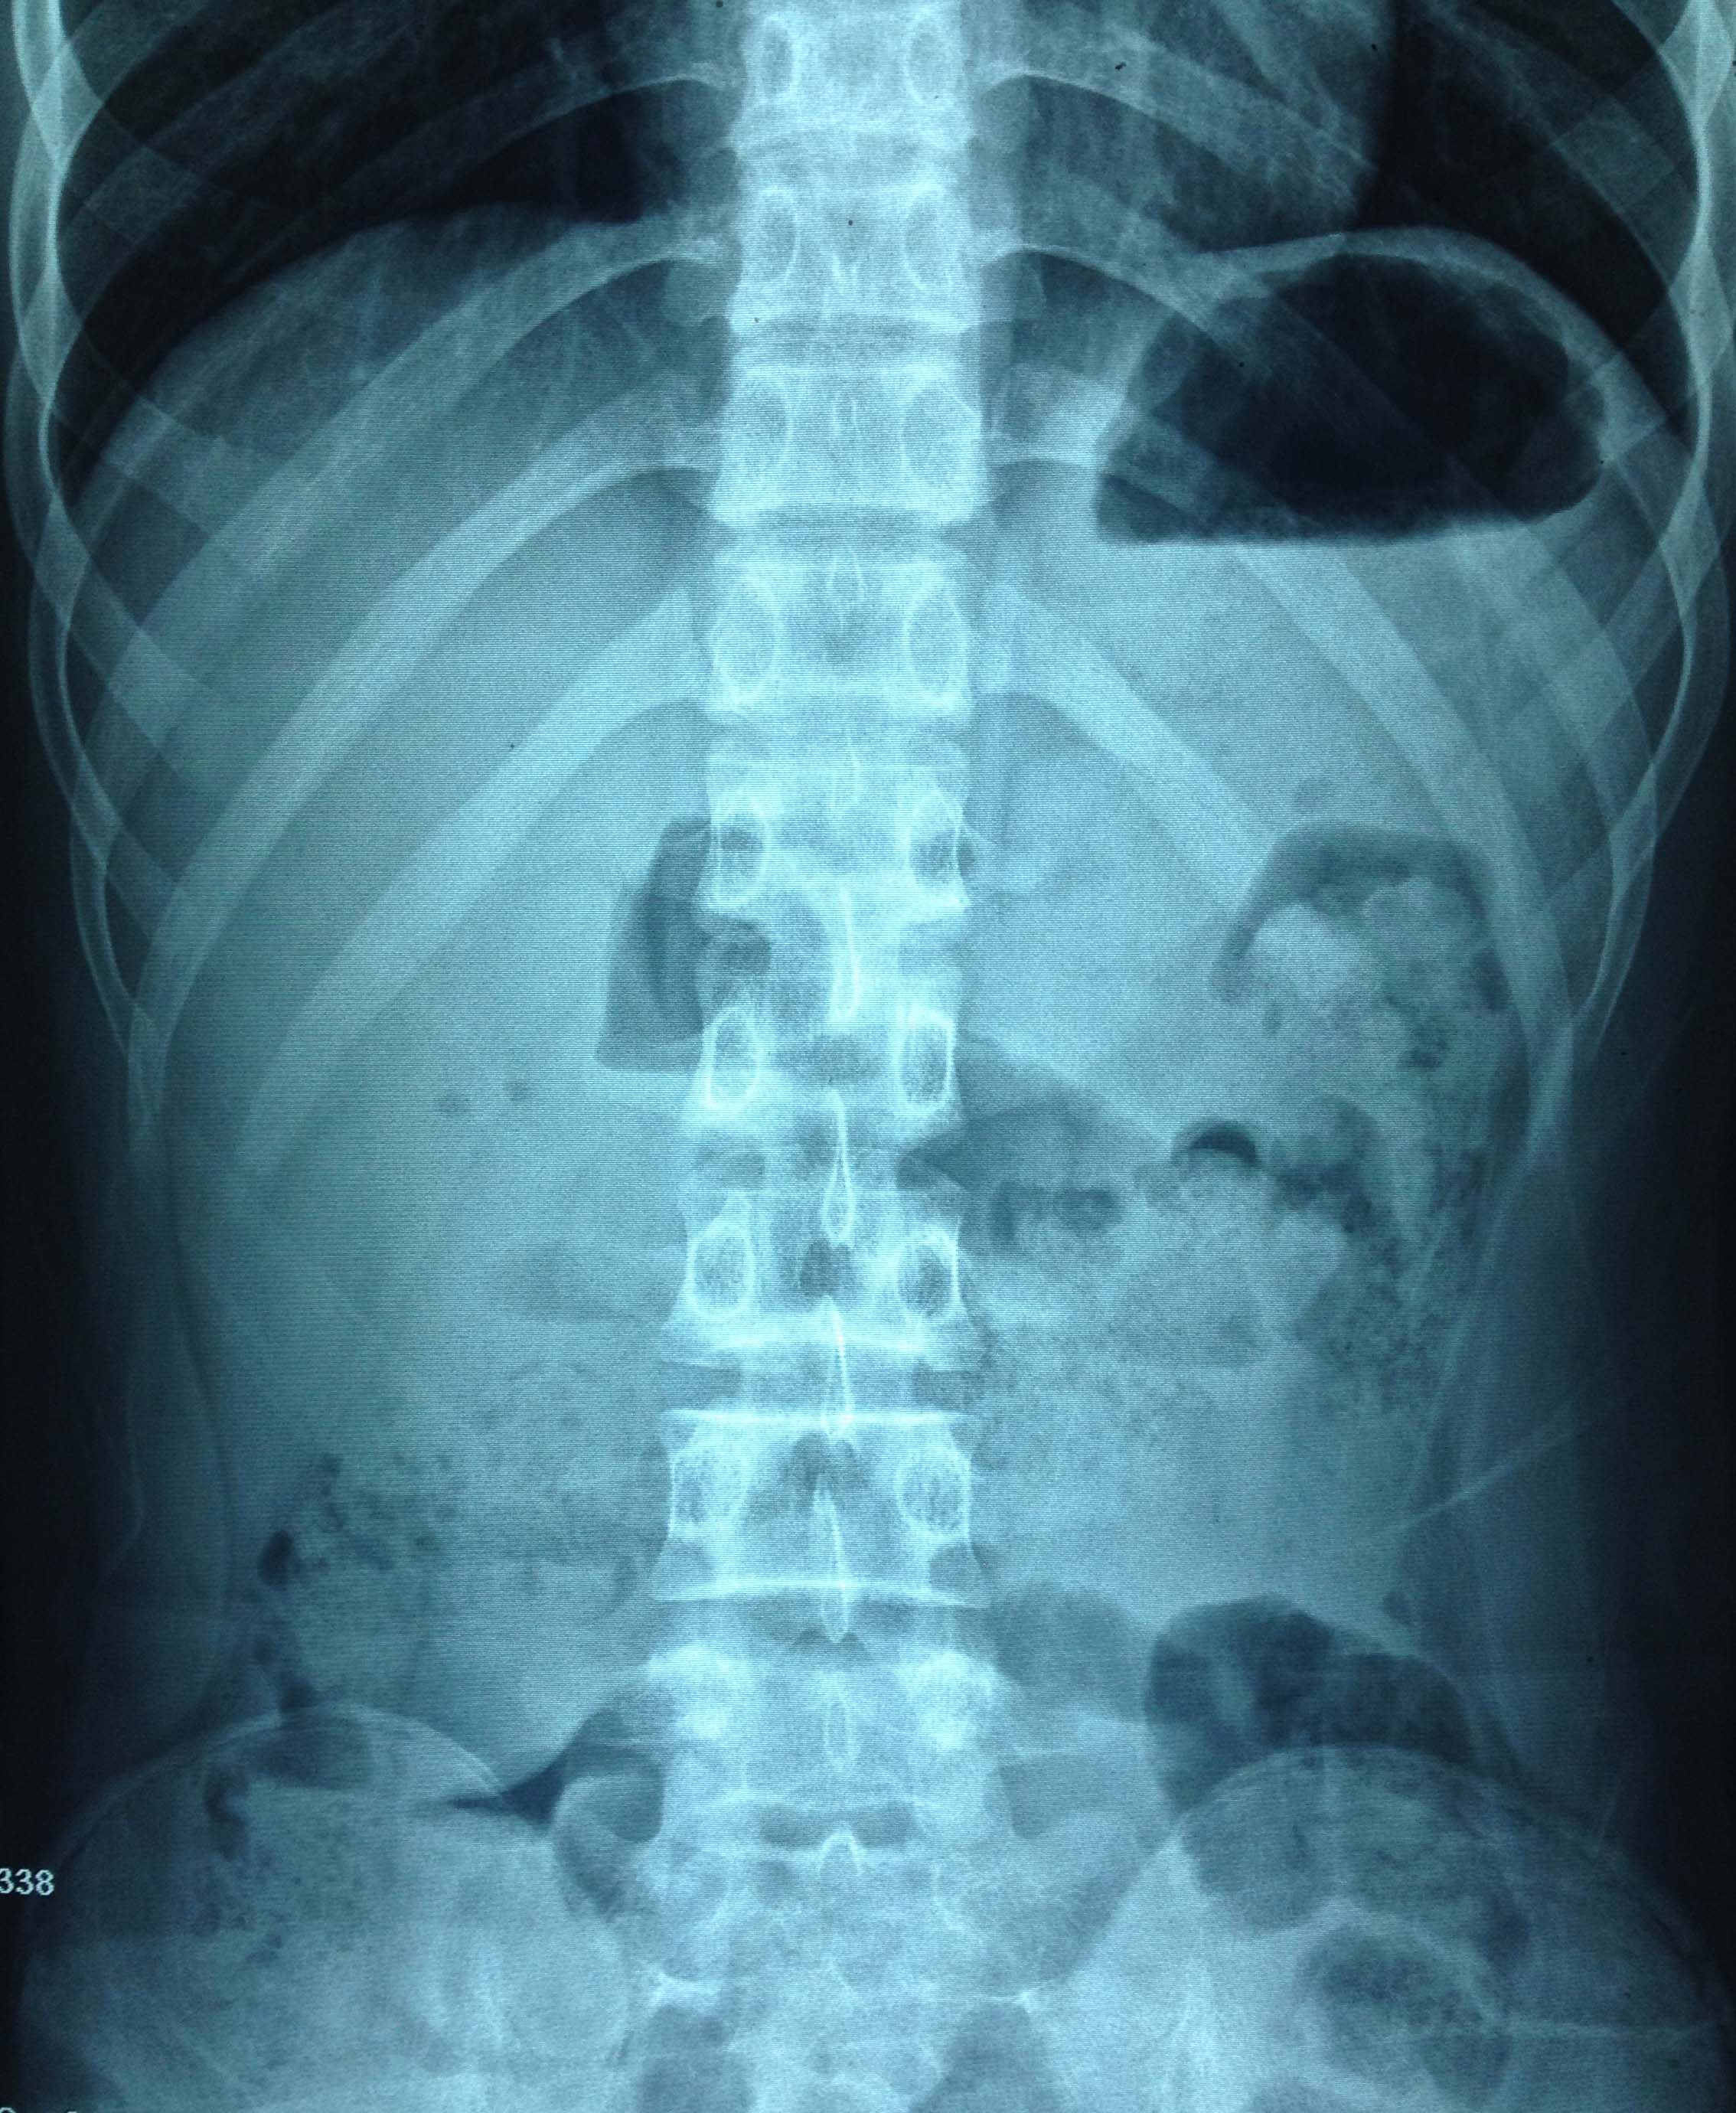

在X线引导下成功植入肠梗阻导管套件